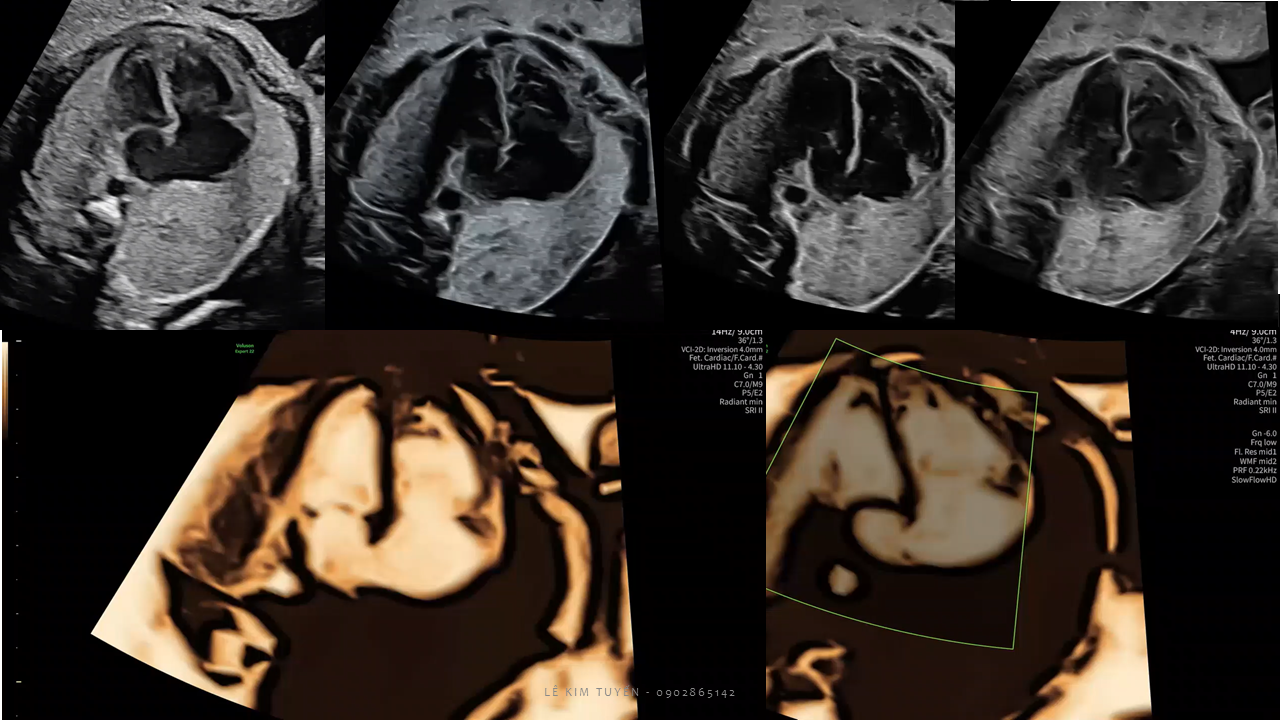

Siêu âm tim thai - Các kỹ thuật hiện đại

TS. BS. Lê Kim Tuyến

Bệnh viện Tim Tâm Đức